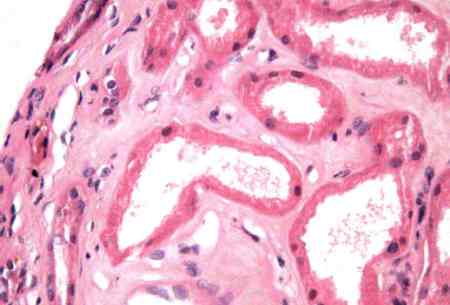

Necrose tubular aguda

Áreas focais de vacuolização tubular proximal e achatamento. Dilatação tubular. Debris da borda em escova em alguns lúmens tubulares

Cortesia da Puigvert Foundation, Barcelona, Espanha